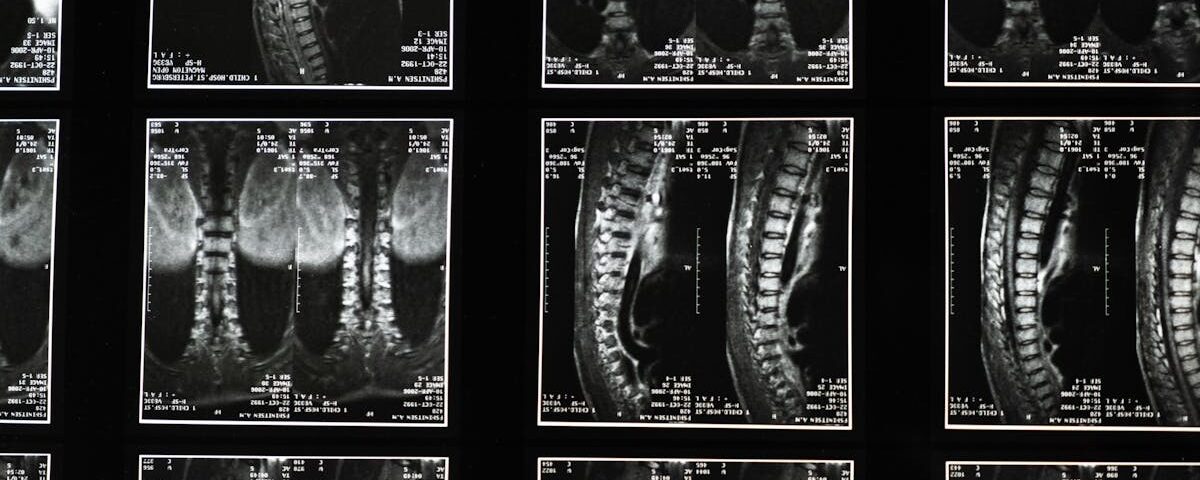

La sciatique est liée à la compression ou à l’irritation du nerf sciatique. Les symptômes peuvent inclure une douleur intense dans le bas du dos et une sensation de picotement dans une jambe. En raison de ces symptômes, il est crucial que le patient partage des détails précis avec son thérapeute. Une description complète des symptômes aide le professionnel à poser un diagnostic approprié.